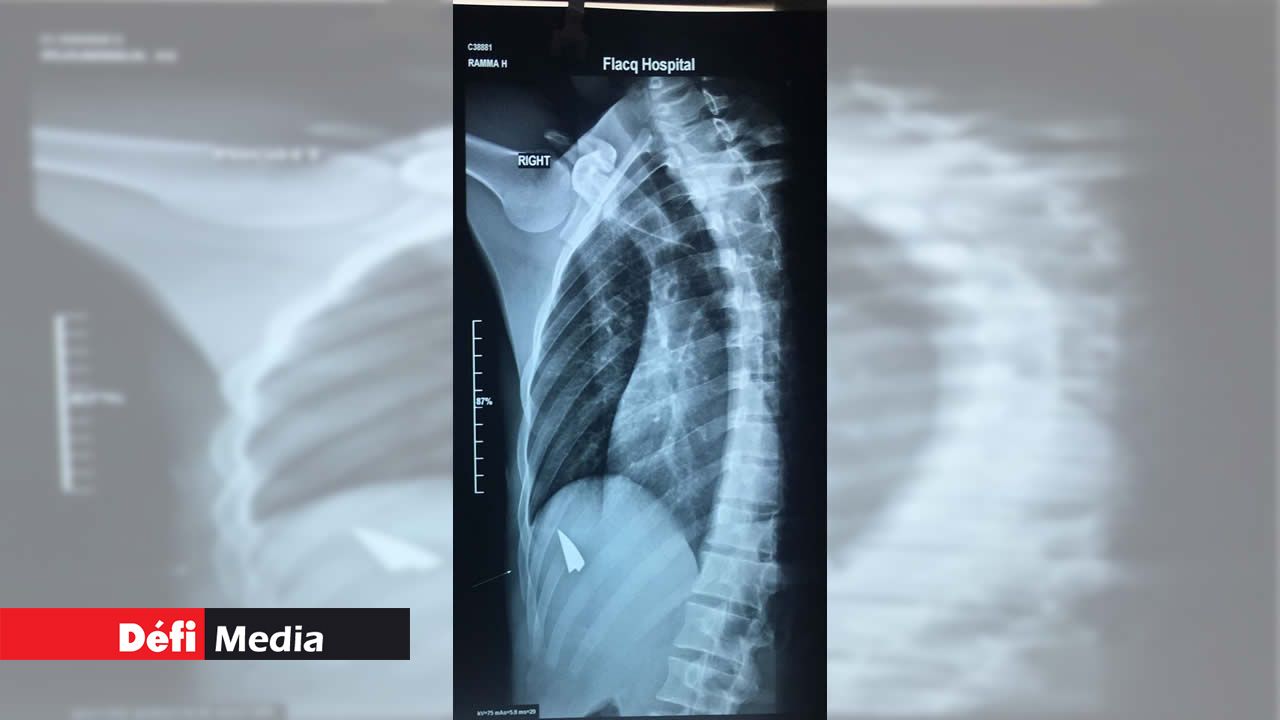

Selon les informations circulées à la suite de l’attaque, le coup de cutter aurait pu être mortel. Les circonstances ont été rapportées à la police qui poursuit son enquête. La tension est montée lorsque les deux protagonistes, un élève du School Certificate (SC) et un autre du Upper 6 ont eu des échanges verbaux sévères. Le premier a alors porté le coup à son aîné, le blessant gravement.

L’élève de Upper 6 a été transporté à l’hôpital. Vu son état, il a été admis. L’enquête de la police est menée parallèlement avec celle du ministère de l’Éducation. Il nous revient que les deux élèves appartiennent à des groupes différents au sein de l’établissement qui ont l’habitude de s’affronter.